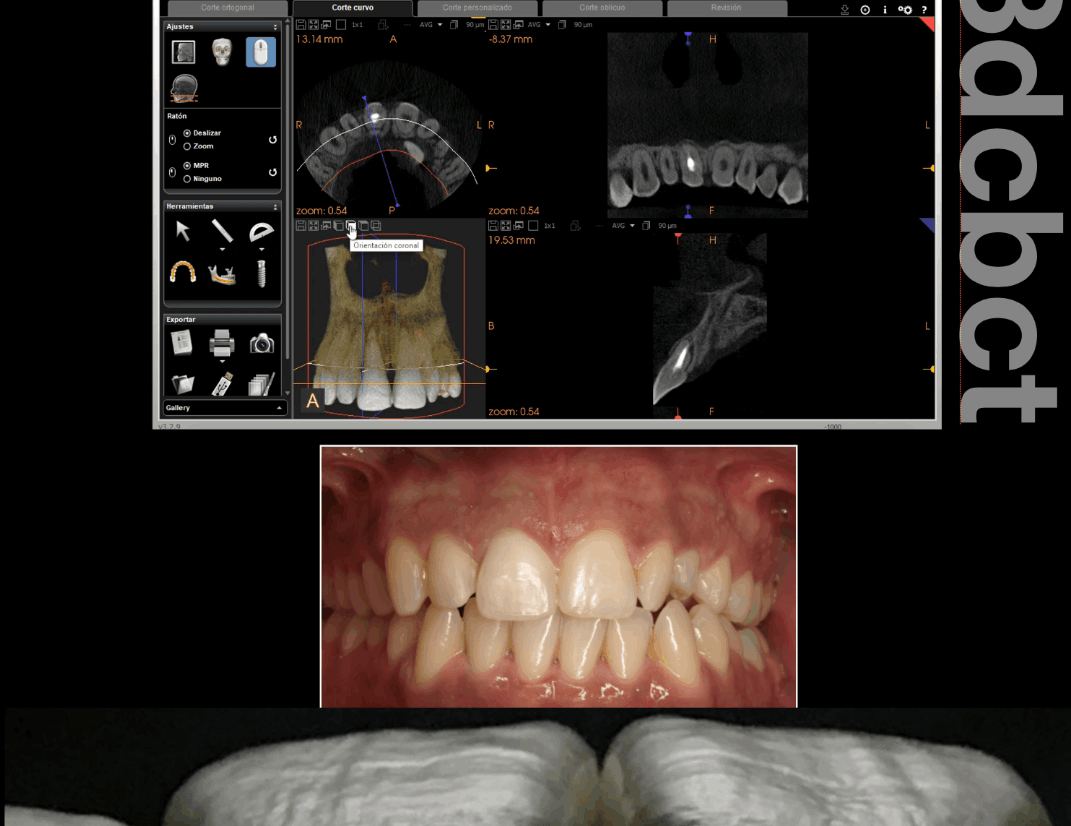

Fisuras

Los dientes fisurados muestran muchos tipos de síntomas, incluido el dolor al masticar, la sensibilidad a la temperatura o incluso la liberación de presión al morder. También es común que el dolor de dientes vaya y venga, lo que dificulta el diagnóstico de la causa del malestar.

La masticación puede causar el movimiento de las piezas fisuradas de su diente, y la pulpa dentro del diente se irrita. Al mismo tiempo, cuando se libera la presión de morder, la grieta puede cerrarse rápidamente, lo que produce un dolor agudo. Eventualmente, la pulpa se dañará y el diente dolerá constantemente, incluso cuando no esté masticando. Es posible que las grietas puedan provocar la infección del tejido pulpar, que puede extenderse al hueso y la encía que rodea el diente.